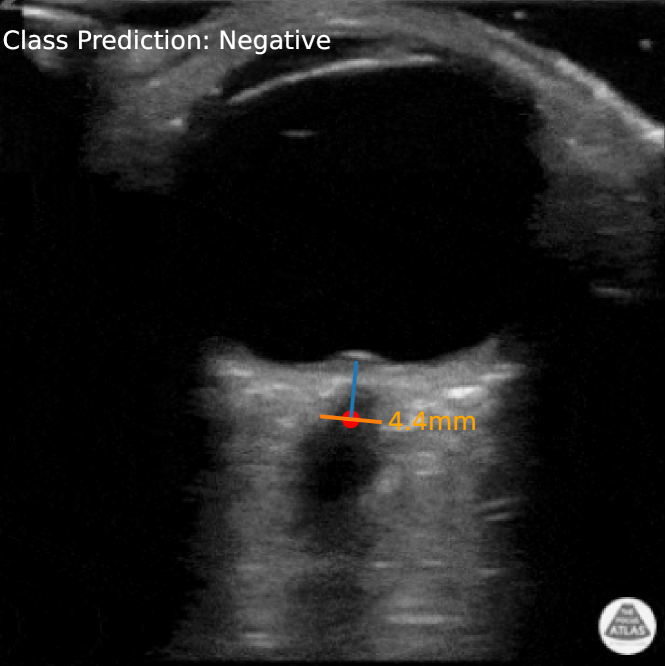

Fig. 1: Output from our R2U-Net-based ONSD measurement system. Each stage of our proposed pipeline surfaces clinically relevant information (colored features rendered on the image) that the model is using to make its final prediction.

In this work, we present two models for elevated ICP detection within the context of an ultrasound video classification task. The first model is a 2D convolutional LCA sparse coding model inspired by the work of Hannan et al. [1]. The second model uses a R2U-Net [2] pipeline to directly predict the width of the nerve by generating a mask at the point of measurement (Figure 1).111Image was acquired from the POCUS Atlas (https://www.thepocusatlas.com/). Both of these models utilize architectures, or are built upon architectures, that have been demonstrated to be effectively run on mobile platforms. We conduct a full set of experiments for both of our proposed models, comparing them to CLIP ViT-B/16 [3] and ConvNeXT [4], two pre-trained models that are exposed to millions of examples. We demonstrate that our proposed models outperform each of these architectures, with our R2U-Net approach exceeding the other models by a large margin. We also conduct a qualitative analysis of this model where a SME assessed its generated predictions, further validating its performance.

As discussed in Section 1, there are a variety of target criteria that must be met in order for an AI system to be suitable for deployment in our application setting. The first of these criteria focused on developing models that are interpretable and easy to use so that they can support the medical examiner throughout the procedure. Our expert-driven decomposition approach to model design allows us to surface relevant information at intermediate states of the model, which would otherwise not be possible in an end-to-end system. In our sparse coding model, some additional feedback is provided to the examiner in the form of a bounding box around the nerve. Our R2U-Net system surfaces even more information (see Figure 1). A blue line extends from the posterior aspect of the ocular globe to the 3mm mark in the nerve, while also indicating the angle in which the optic nerve approaches the retinal plane, the red dot indicates the point of measurement, and the orange line corresponds to the predicted width. These artifacts accurately represent the actual values that the model is using to make its prediction, rather than some approximation generated by a post hoc method. The information provided by our system can serve many different purposes depending on the target user. If the user is an expert, it may simply speed up image interpretation. If the user is a non-expert, such as a battlefield medic, it may fill gaps in their understanding and enable them to successfully collect a measurement.